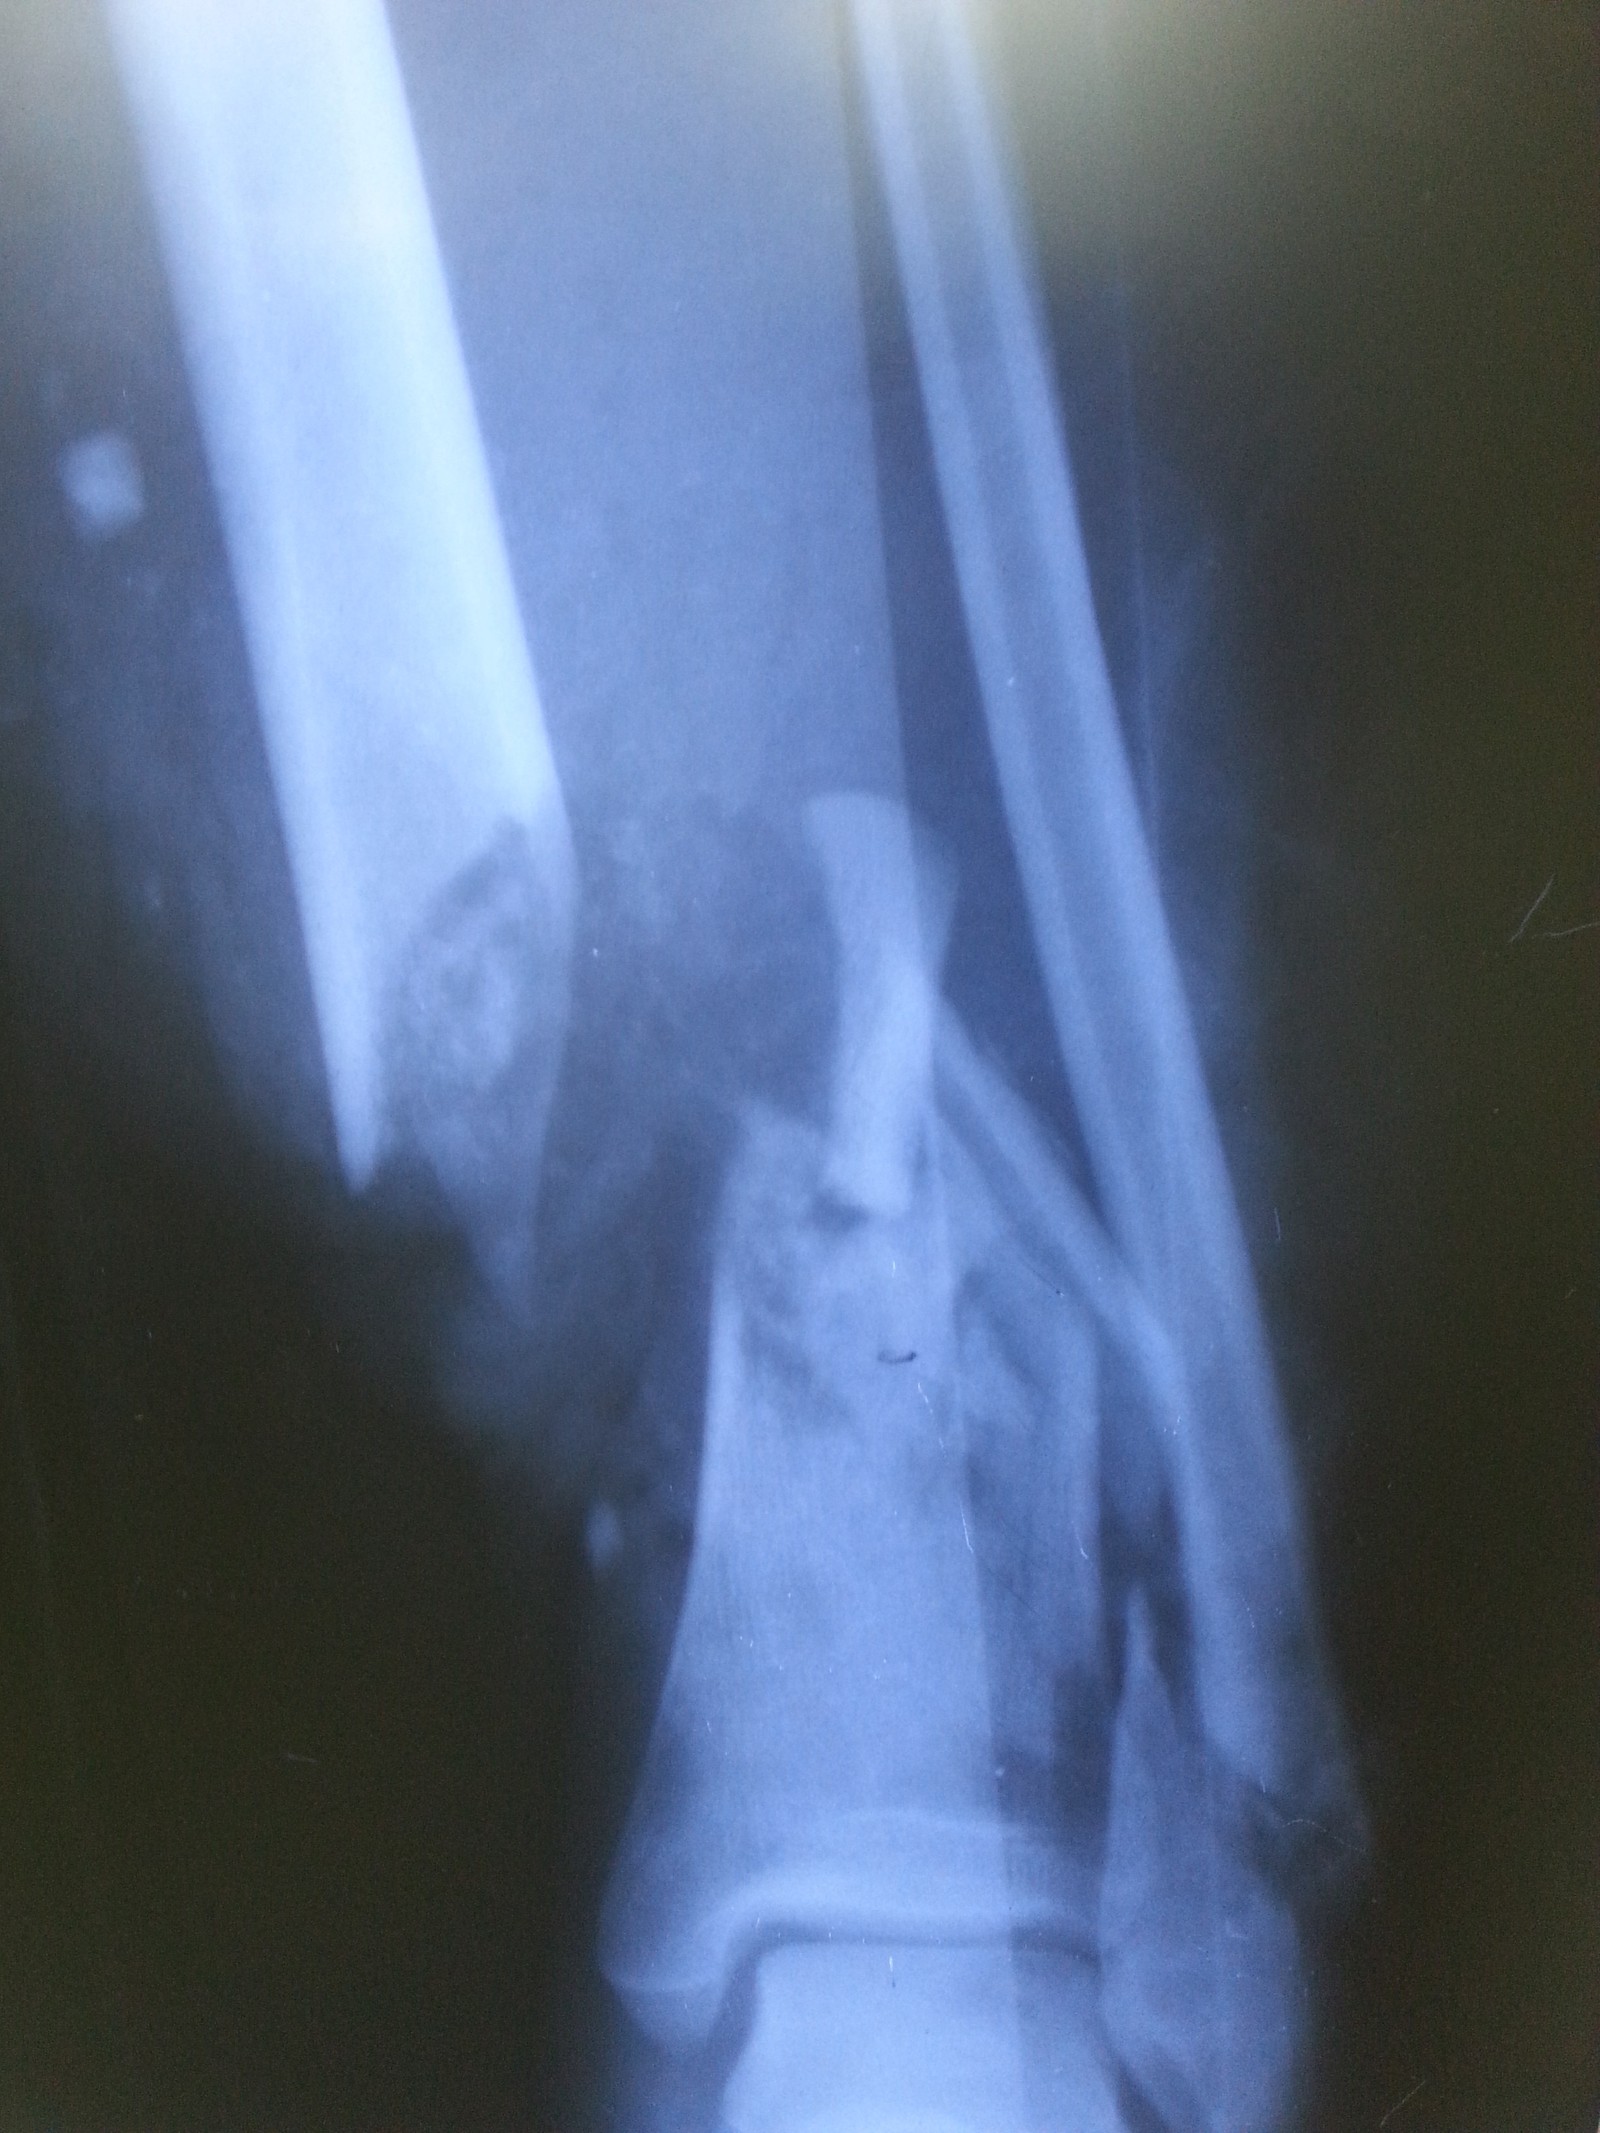

Открытый Перелом Фото

Открытый Перелом Фото 112 фото